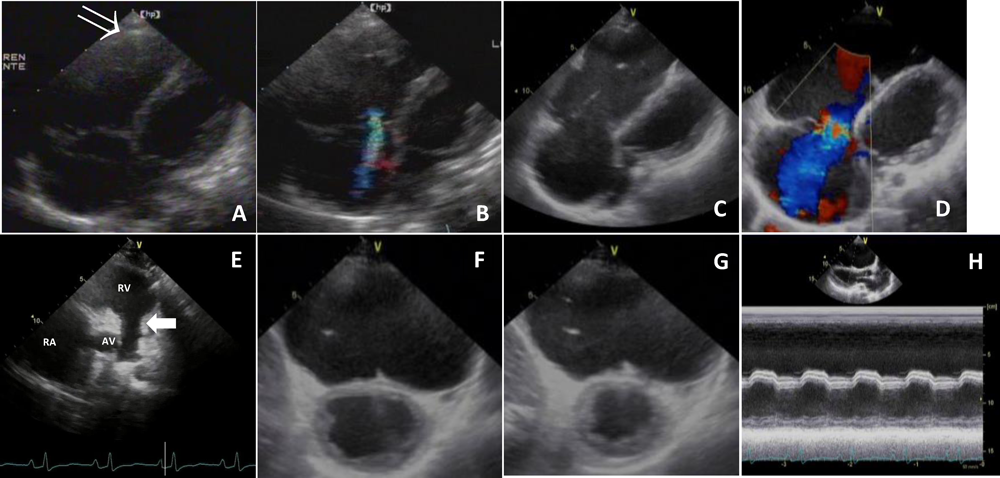

Fig. 2 Four-chamber view at the age of 2-months showing a dilated right ventricle with tricuspid valve leaflets arising appropriately from the annulus (A), thin-walled right ventricle (arrow) and mild tricuspid regurgitation (B). Four-chamber view at the age of 17-years showing his dilated right ventricle and right atrium with severe tricuspid regurgitation (C, D). Short-axis view at the age of 17-years showing diastolic opening of the pulmonary valve (arrow) (E), and, left ventricle dysfunction with interventricular septum paradoxical motion [short-axis view: F (diastolic phase), G (systolic phase); long-axis view: H]

在胎41週,2,820 g,経腟分娩で出生.生後2ヶ月時に心音の減弱と心拡大(CTR 0.60)を指摘され,精査加療目的で紹介入院となった.入院時,体重5,660 g(+0.2 SD)と体重増加は良好であったが,奔馬調律を聴取し,胸部単純X線では著明な心拡大(CTR 0.65)を認めた.心電図にて右房負荷によるP波増高,V1~V6誘導で陰性T波,右側胸部誘導でQRS波低電位を認め(Fig. 1),Holter心電図では単源性心室期外収縮(282回/日)を認めた.心臓超音波検査では,左室は心室中隔を除いて壁運動は良好(LVEF 73%)であったが,右室は著明に拡大し,心室中隔は奇異性運動を呈し,菲薄化した右室壁運動は著しく低下していた(Fig. 2).三尖弁の付着異常などの形態異常はなく,三尖弁閉鎖不全も軽度で肺動脈弁は拡張期に開放していたことから,Uhl病と診断した.右心不全症状を認めなかったが,利尿剤と右室内血栓予防目的でのaspirinの内服を開始し,外来経過観察とした.

Uhl病に対してOne and a half ventricle repairやTCPC等の右心バイパス術が施行され,良好な術後経過が報告されている.Takizawaらは乳児期に診断されたUhl病5例を集計し,右心バイパス術を施行した4例の中期成績は良好であったと報告している3).しかし,Uhl病が稀な疾患であることから,その治療介入後の報告数も少なく,治療介入時期や治療戦略も一定していない.自験例では右心不全症状が乏しかったことから,経過観察の方針とした.9歳時にグレン手術/右室縫縮術を提示したが,セカンドオピニオンを希望して他院を受診した結果,家族は外科的治療を希望しなかった.その後,MATを認め,右室だけでなく左室機能低下も呈していることから(Fig. 2),心臓移植を含めた外科的治療介入を検討している.左室機能低下の要因として心筋欠如が左室に及んでいる可能性を考慮したが,MRI上は左室の心筋細胞欠如を認めなかったことから,継続的に拡張する右室によって左室が圧排され,左室機能が低下したと考えられた.Ebstein奇形では,左室容量は維持されつつ左室機能低下を来すことが知られており,拡張した右室による圧排によって左室形態が変形することがその要因と考えられている10).Uhl病でもEbstein奇形と類似した機序によって左室機能低下がもたらされると思われた.